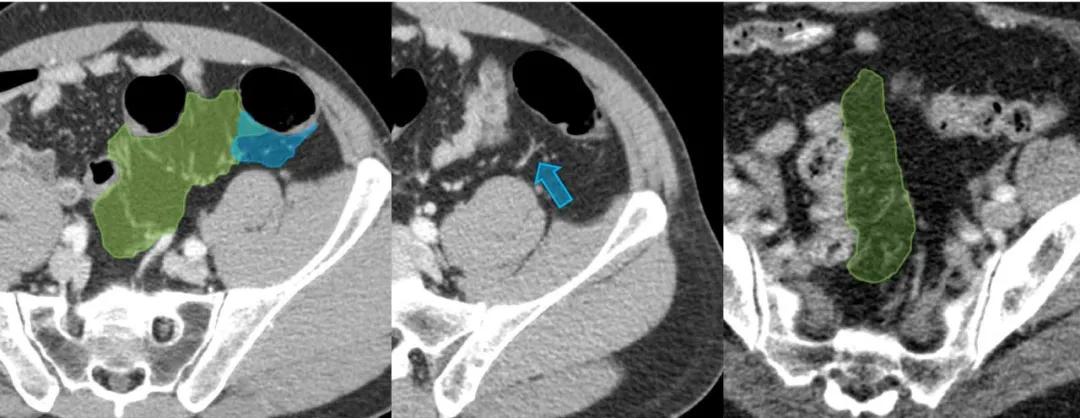

乙状结肠系膜(绿色)与左侧结肠系膜的汇合处(蓝色),降结肠动脉(蓝色箭头)。